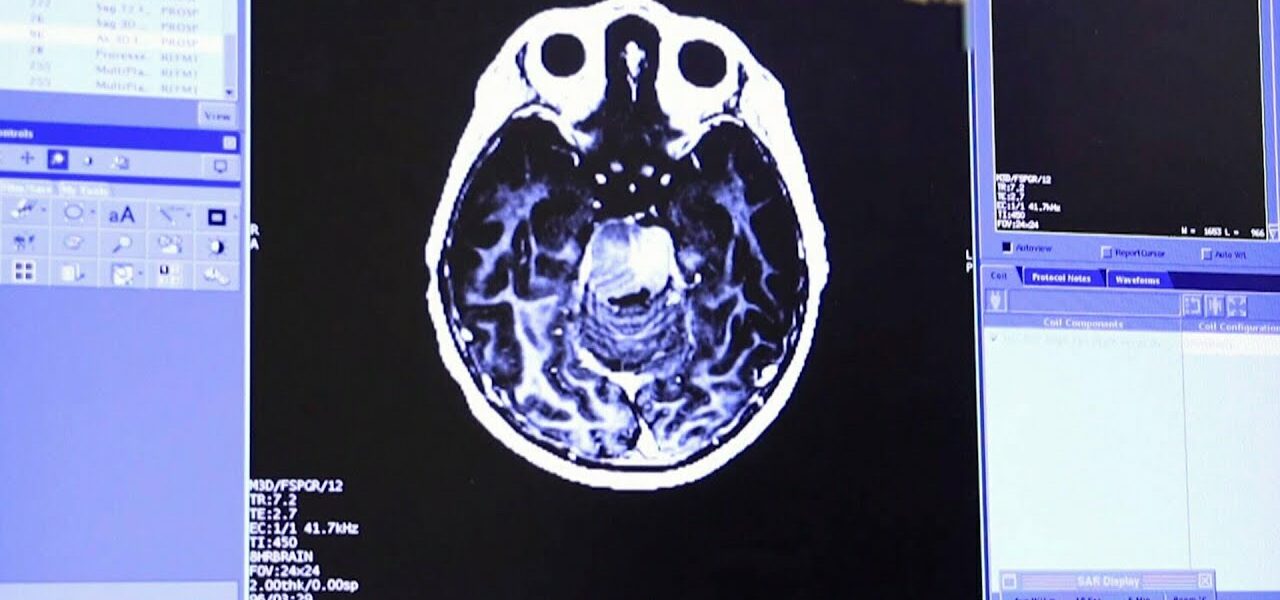

In a world-first, Canadian doctors were able to treat a child’s inoperable brain tumour by delivering chemotherapy through an ultrasound.